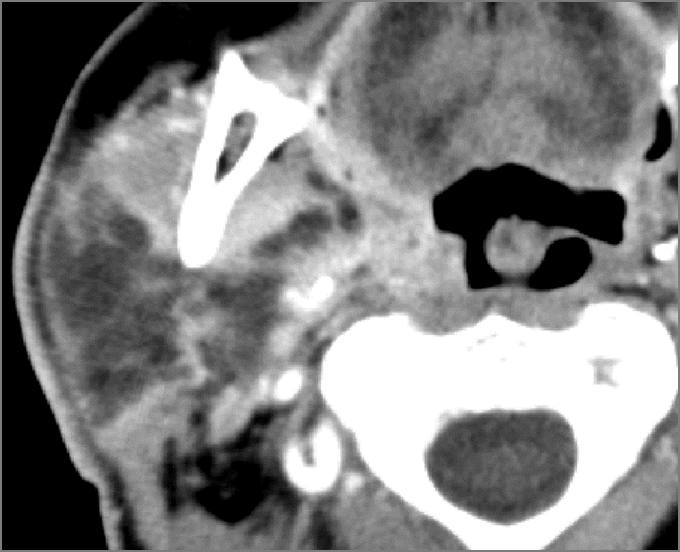

There is excessive enhancement or thickening of the fat or other soft tissues within or surrounding the buccal space, masticator space, floor of the mouth, submandibular space or the adjacent superficial fascia or subcutaneous fat and skin. [Yes/No]

There is subperiosteal abscess or an abscess cavity adjacent to or involving the maxilla or mandible. [Yes/No]

There is endodontal or periodontal disease that might be causing cellulitis or abscess. [Yes/No]

The lingual or buccal aspect of the maxilla is eroded. [Yes/No]

The lingual or buccal aspect of the mandible is eroded. [Yes/No]